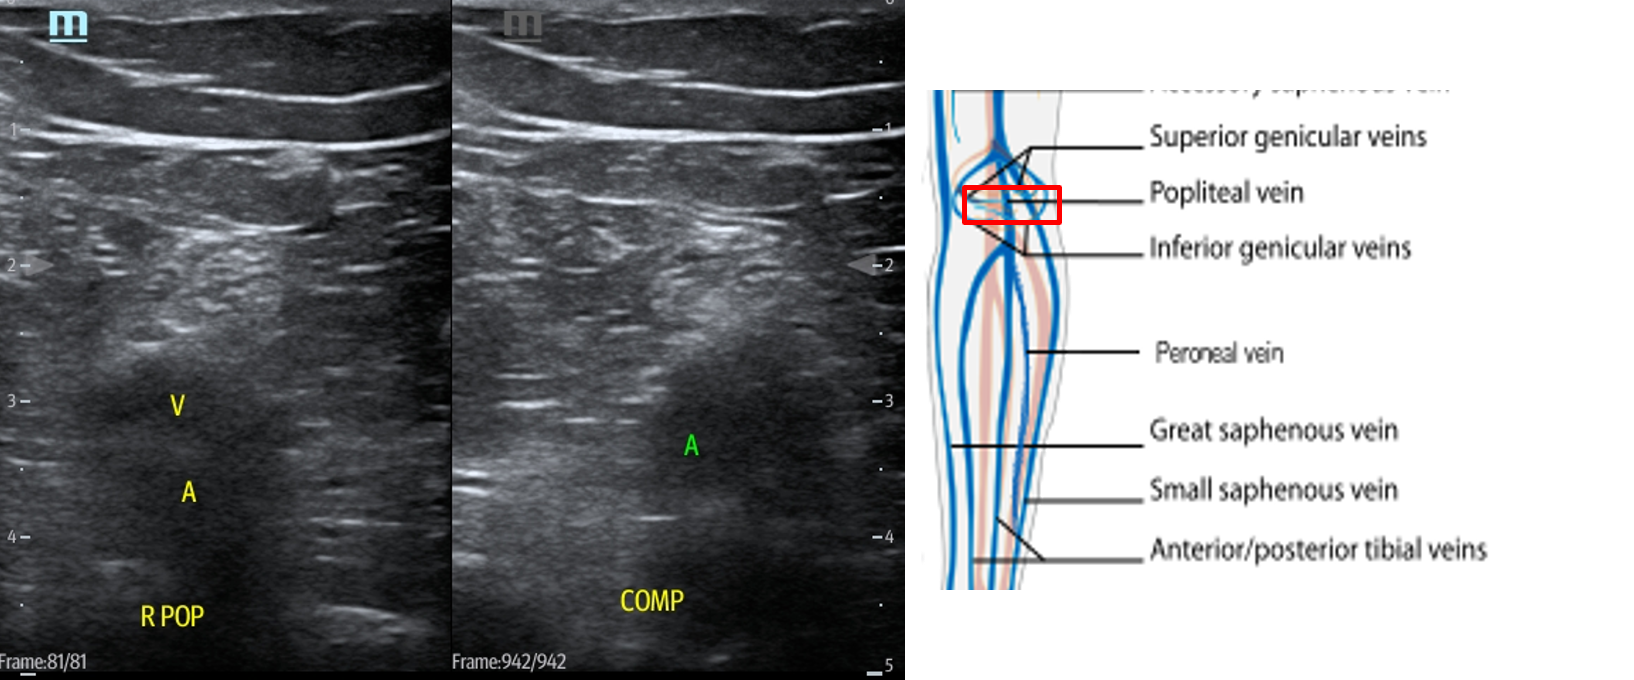

- In the popliteal region, you should see the popliteal vein (PV) superficial to the popliteal artery (PA). (Fig. 14) If you see more than one artery and one vein, slide the transducer proximally until you see the PV and PA. When you have this view, compress as before.

- Figure 14. Compression of the popliteal vein in the popliteal fossa with transducer orientation indicated (red rectangle).

- Slide the transducer distally until you see the PV trifurcate into the PTV, ATV and peroneal vein. (Fig. 15) Compress each of these veins. This constitutes completion of evaluation of “region 2.”

- Figure 15. Compression of the PTV, ATV and peroneal vein in the distal portion of the popliteal fossa just before they converge into the popliteal vein with transducer orientation indicated (red rectangle).